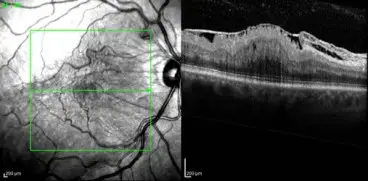

Ηλικιακή Εκφύλιση Ωχράς Κηλίδας

Ο αμφιβληστροειδής είναι ένας λεπτός χιτώνας στο πίσω μέρος του οφθαλμού (παίζει τον ρόλο φωτογραφικού φιλμ για την αποτύπωση των οπτικών πληροφοριών). Η ωχρά κηλίδα…